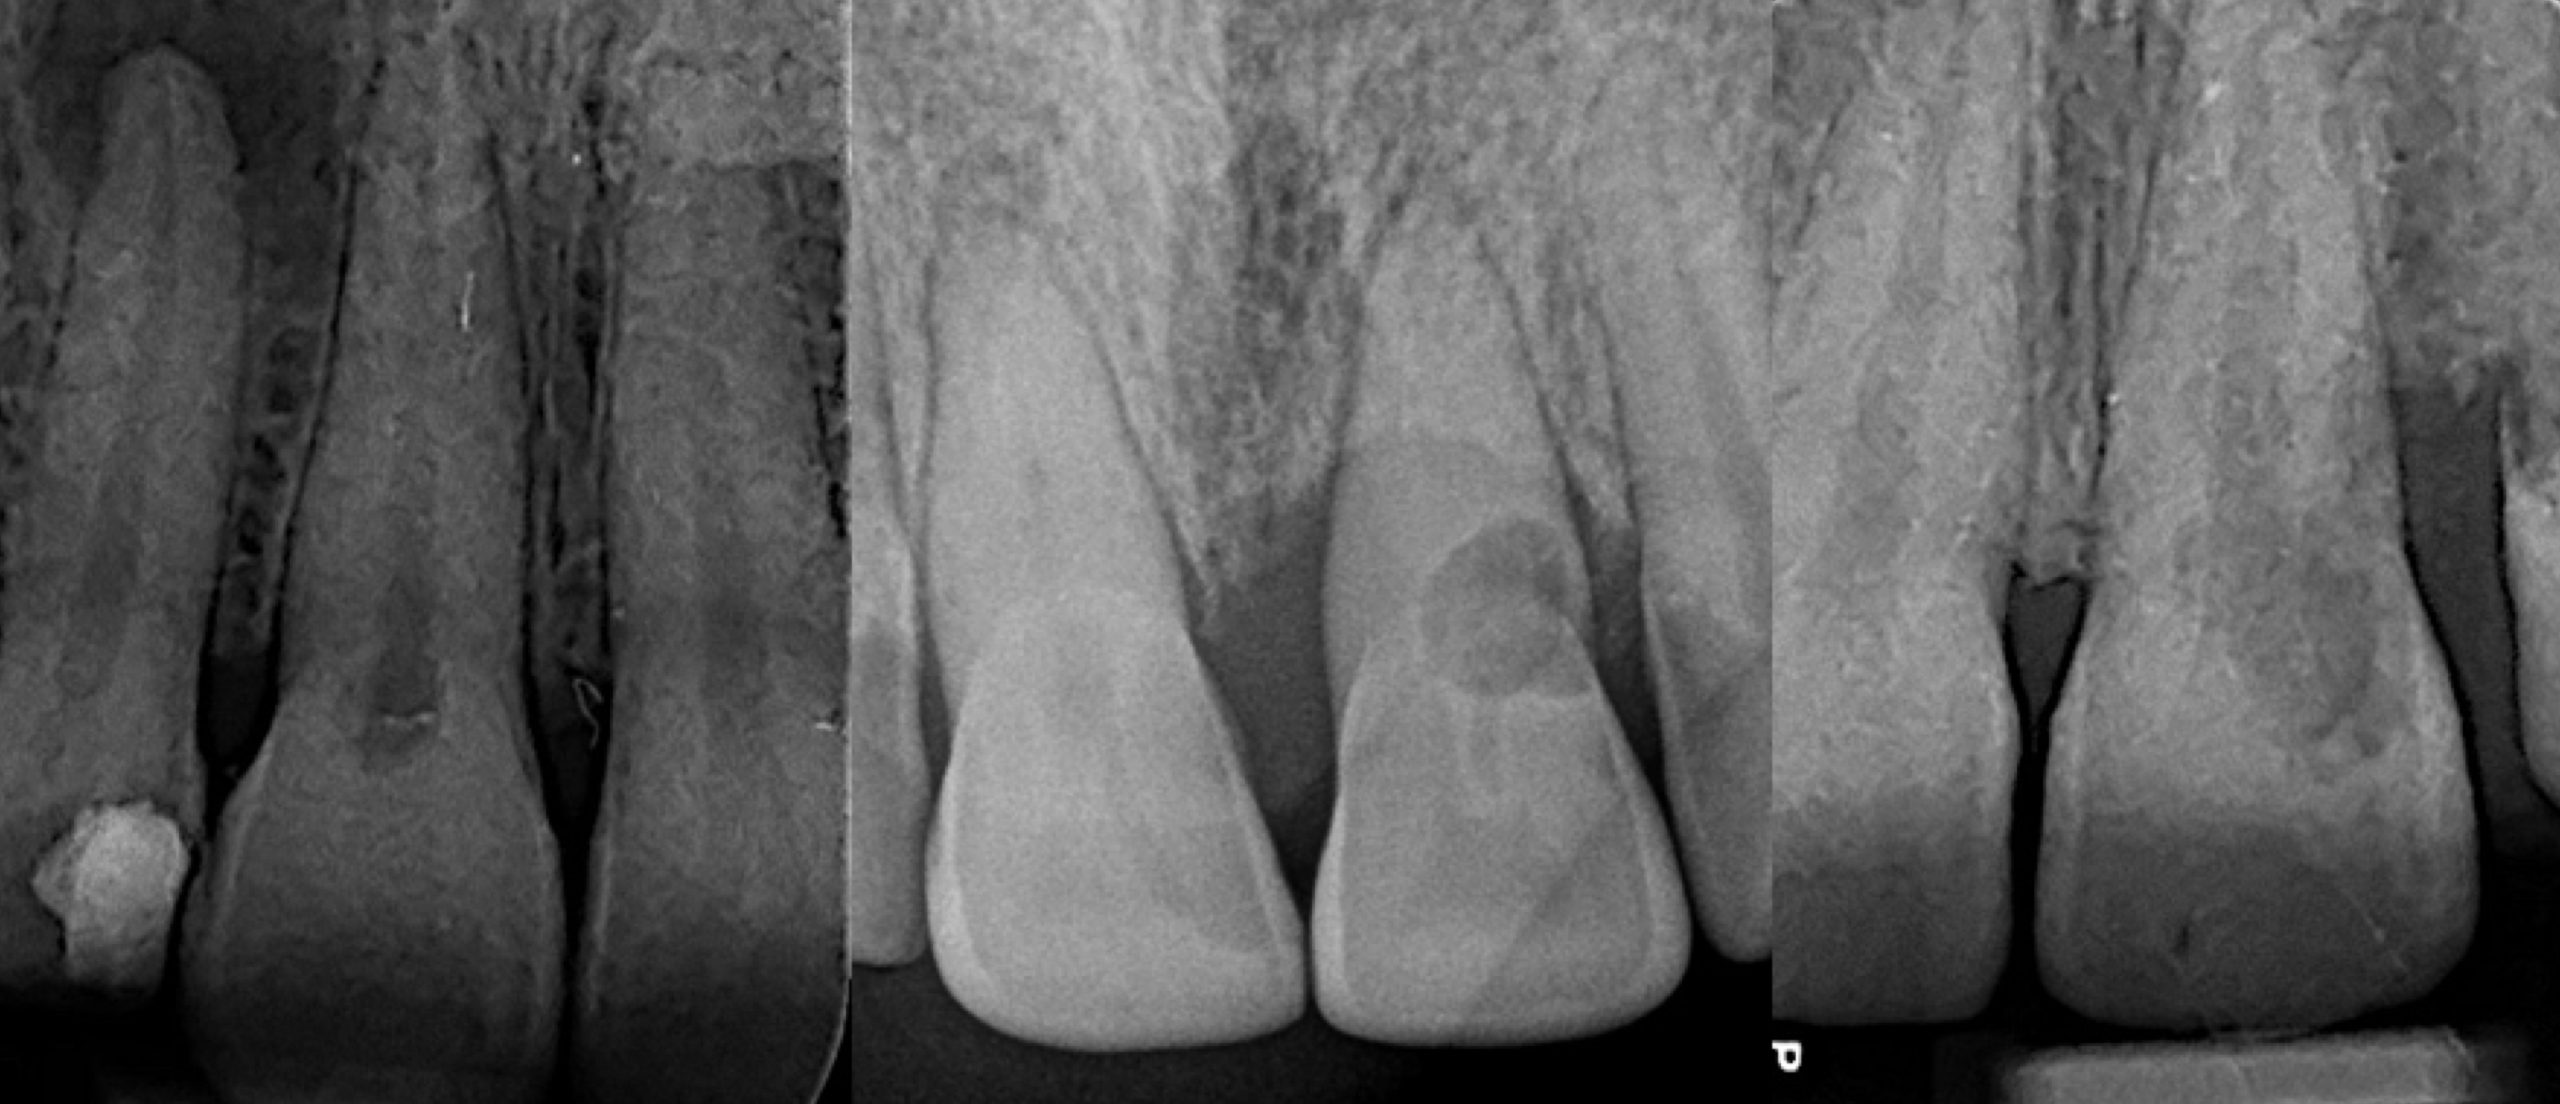

Dens invaginatus is malformation of teeth probably resulting from an infolding of the dental papilla during tooth development. Affected teeth show a deep infolding of enamel and dentine starting from the foramen coecum or even the tip of the cusps, and which may extend deep into the root. Teeth most affected are maxillary lateral incisors and bilateral occurrence is not uncommon. The malformation shows a broad spectrum of morphologic variations and frequently results in early pulp necrosis. Root canal therapy may present severe problems because of the complex anatomy of the teeth.